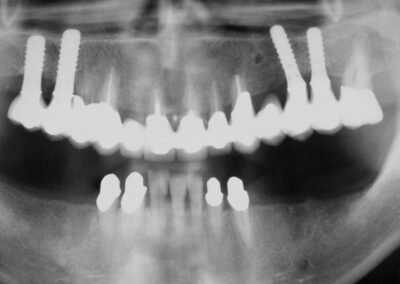

Übersichtsaufnahme einer 50jährigen  Patientin,  die sich im Herbst 1999 mit einer alten, insuffizienten prothetischen Versorgung im Oberkiefer bei uns vorstellte, um mögliche Aternativen zu der ihr angeratenen Neuversorgung mit einer Totalprothese respektive zu einer auf 4 Implantaten stegreitenden Prothese zu besprechen..